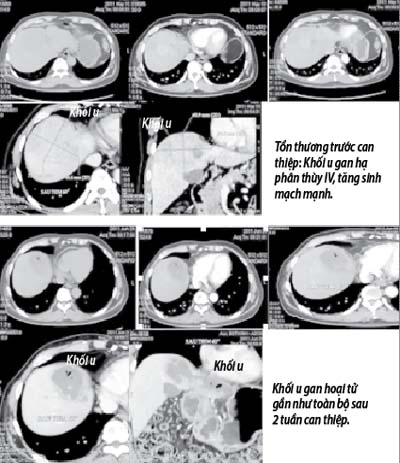

Tuy vậy, trong lần kiểm tra sức khỏe định kỳ năm 2011, bác sĩ phát hiện ông có khối u gan tái phát với kích thước 8cm ở hạ phân thùy IV, tăng sinh mạch mạnh. Đối với căn bệnh UTBMTBG, để điều trị cho người bệnh đòi hỏi phải được phát hiện sớm và phương pháp phẫu thuật cắt bỏ khối u vẫn là hiệu quả nhất. Khi bệnh nhân đã có triệu chứng lâm sàng như đau vùng gan hoặc gày sút cân nhanh thì đây thường là giai đoạn bệnh tiến triển và phương pháp điều trị tạm thời cơ bản là hóa tắc mạch qua đường động mạch hay còn gọi là phương pháp hóa tắc mạch truyền thống.

Ngày 3/6/2011, bệnh nhân Đ. đã được chỉ định điều trị UTBMTBG bằng phương pháp hóa tắc mạch với hạt vi cầu DC Beads (DCB). Sử dụng hạt DCB với 2 loại kích cỡ: 1ml loại hạt đường kính 100 - 300 micromet và 1ml loại hạt đường kính 500 - 700 micromet. Mỗi loại kích cỡ hạt được tải với 37,5mg doxorubicin (hóa chất chống ung thư). Thời gian tải 60 phút cho loại kích cỡ nhỏ và 90 phút cho loại kích cỡ lớn… Sau can thiệp, bệnh nhân chỉ nằm viện 5 ngày và xuất viện trong tình trạng sức khỏe tốt, ăn ngủ bình thường, không sốt, hết đau vùng gan, men gan gần như bình thường và hiện nay vẫn có thể chơi thể thao hàng ngày. Đây là bệnh nhân đầu tiên được can thiệp bằng phương pháp này và đáp ứng điều trị tốt.

Đến nay, Bộ môn – Khoa nội tiêu hóa, Bệnh viện TWQĐ 108 đã thực hiện thành công kỹ thuật hóa tắc mạch với hạt vi cầu cho hơn 30 bệnh nhân UTBMTBG và diễn biến tình trạng bệnh của đa số các bệnh nhân đều tốt. Những bệnh nhân đáp ứng tốt với phương pháp điều trị này đều có kích thước khối u đã được thu nhỏ so với trước khi điều trị.